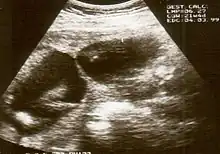

![]() | |

| An infant's hand affected by constriction ring syndrome | |